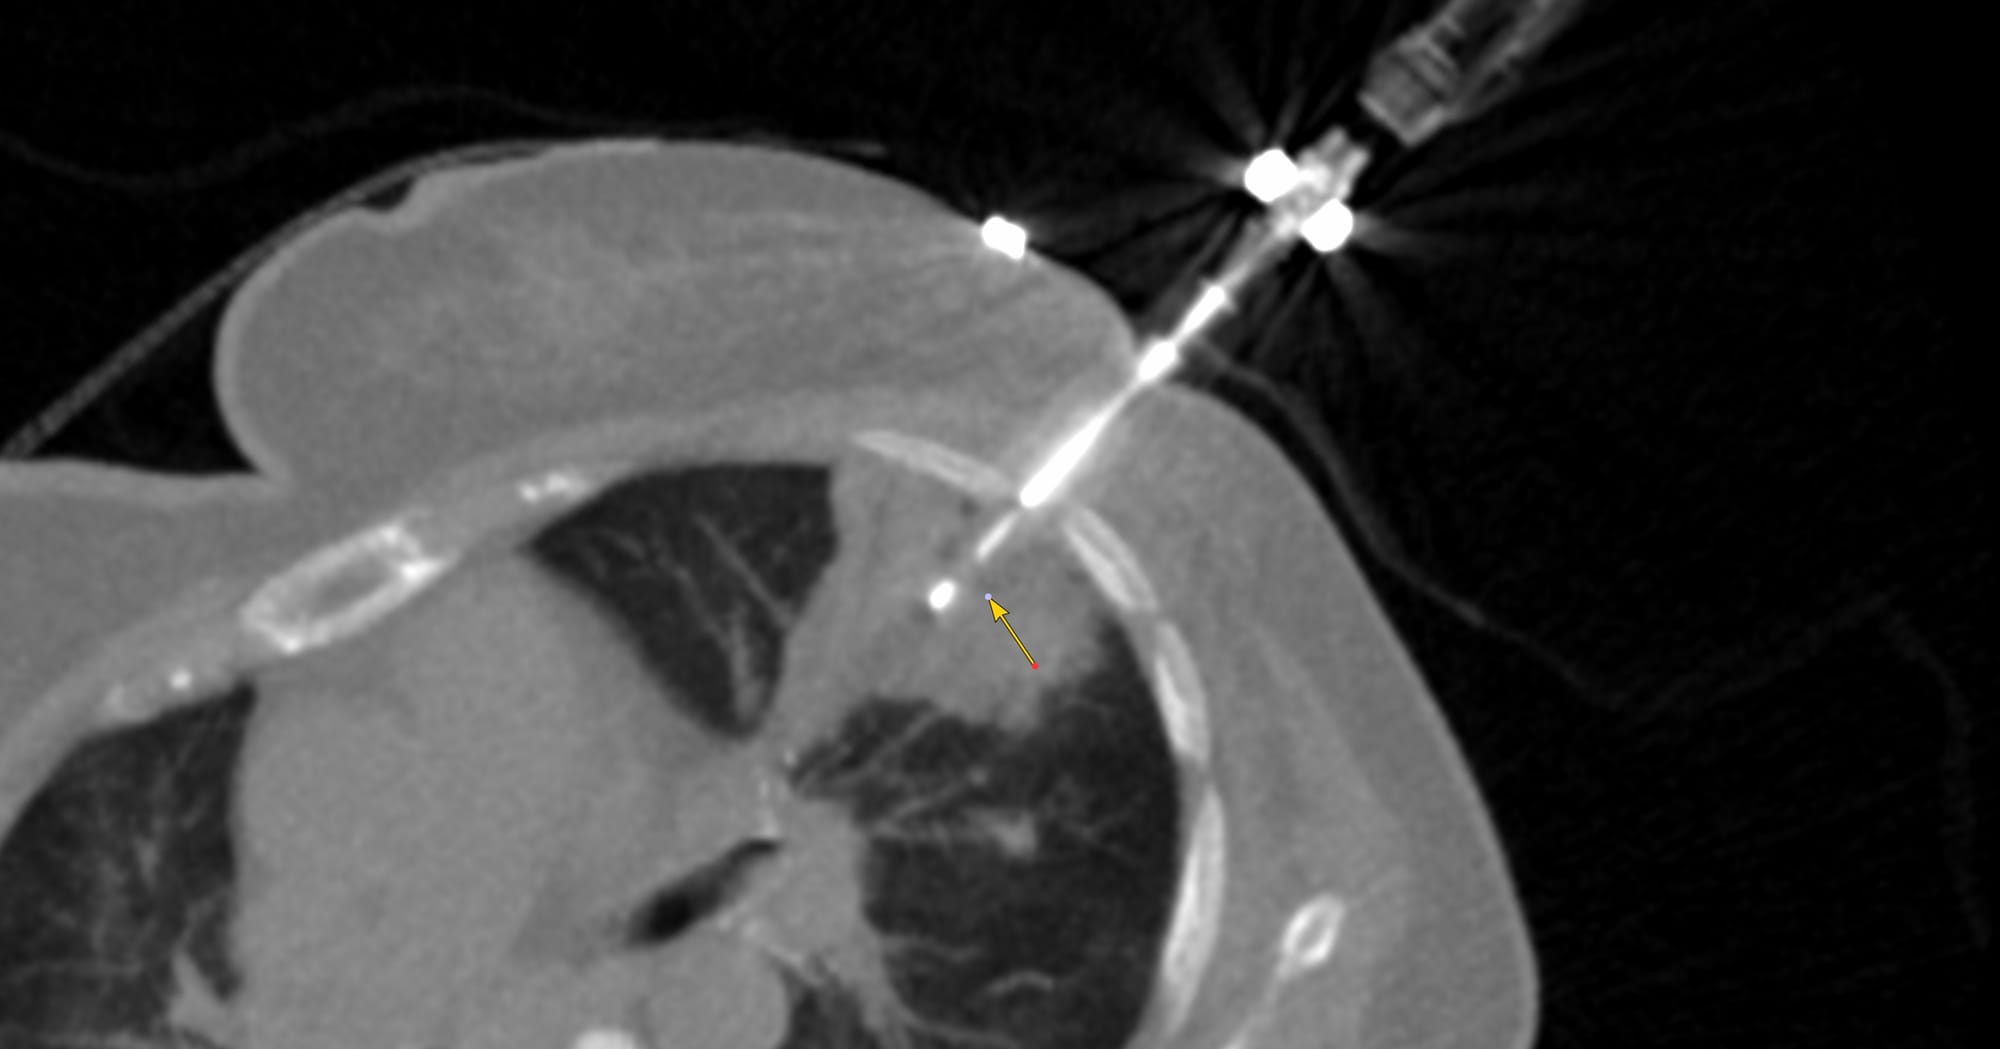

Case 2: Small lung nodule - 6-10 mm (7.8 mm)

Bhavin Jankharia - 07 February 2021